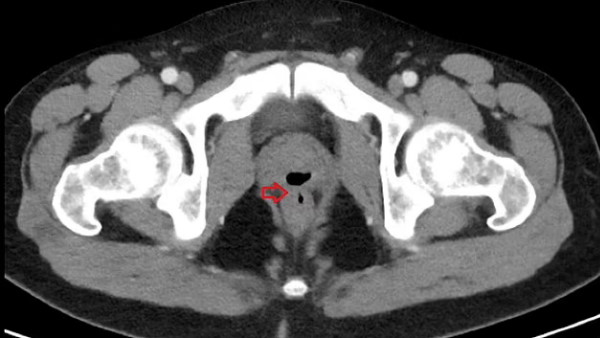

जब उस व्यक्ति पर दर्द सहन नहीं हुआ तो वह डॉक्टर के पास पहुंचा। डॉक्टर्स ने जांच में पाया कि उसके प्राइवेट पार्ट्स के साथ एक मेडिकल गलती के कारण ऐसी छेड़छाड़ हुई थी। मेडिकल जर्नल क्यूरियस में प्रकाशित एक पेपर के अनुसार, परीक्षणों से पता चला कि उन्हें मूत्र मार्ग में संक्रमण के साथ-साथ उनकी मलाशय की दीवार में भी समस्या थी। सीटी स्कैन से पता चला कि उसके पेट के अंदर 'गैस से भरी संरचना' थी, आगे के परीक्षणों से मूत्रमार्ग और मलाशय के बीच एक फिस्टुला मिला।

अस्पताल में कोमा के दौरान फॉले कैथिटर डालते समय उसके शरीर में एक सुरंग बन गई। जो प्रोस्टेट और मलाशय को जोड़ रही थी। इसके चलते शख्स के टेस्टिकल्स सूज गए थे। इतना ही नहीं उसकी बॉडी के अंदर गैस बनने की वजह से यूरिन और सीमन उसके रेक्टम में जमा होने लगा था। इस पूरी गड़बड़ी की वजह से शख्स की बॉडी में इन्फेक्शन हो गया था।